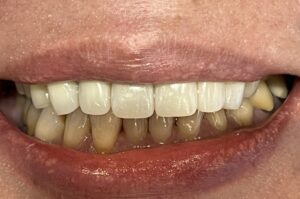

こちらが実際のセット後の写真です。

上の犬歯から犬歯までの6本の歯に審美治療を行っています。

治療のタイミングが異なるため

メタルセラミック、レイヤリングジルコニア、

ジルコニアラミネートべニア(付け爪のように薄いジルコニアを張り付ける方法)

等の材料をつかっています。

スーパーセラミスト常泉氏(ホームページ参照)が丹念に製作しております。

自然で美しい仕上がりに満足いただけています。